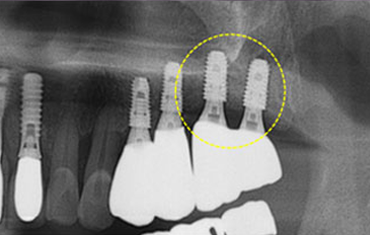

치료 후윗턱뼈 공기주머니에 뼈이식

치료 전

치료 후